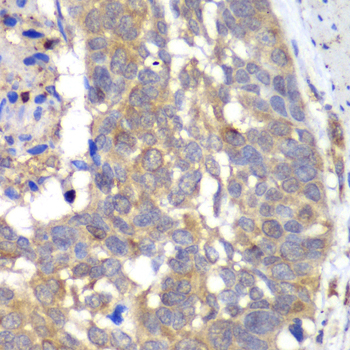

Immunohistochemistry of paraffin-embedded rat liver using HAPLN1 at dilution of 1:100 (40x lens).

Immunohistochemistry of paraffin-embedded human esophageal cancer using HAPLN1 at dilution of 1:100 (40x lens).

Immunohistochemistry of paraffin-embedded human gastric cancer using HAPLN1 at dilution of 1:100 (40x lens).